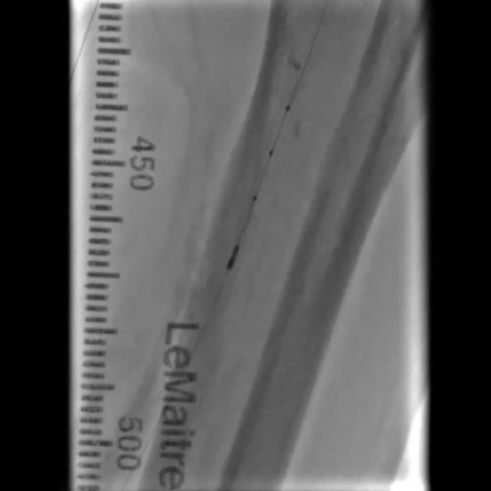

铁基可降解支架植入

按计划植入3×38mm载药铁基可降解支架,准确定位以完全覆盖病变;采用8 atm压力球囊扩张释放支架,确保支架充分张开。